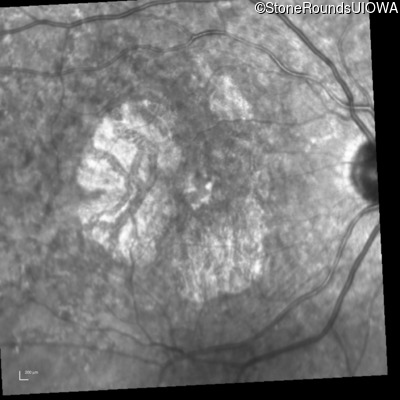

Infrared Fundus Photograph - Right - 20/25 +2

Exemplar

Infrared Fundus Photograph - Left - 20/20 -2